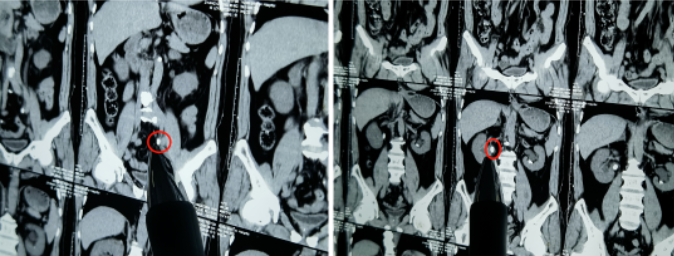

据接诊医生初步判断,很可能是因为结石堵塞输尿管导致无法排尿。在抽血化验后发现,此患者肌酐高达1214umol/L是正常人的10倍!(正常为53-123umol/L),且通过CT诊断,确实有两颗明晃晃的结石卡在了双肾输尿管上段。

(左肾及右肾输尿管上段均被结石卡住)